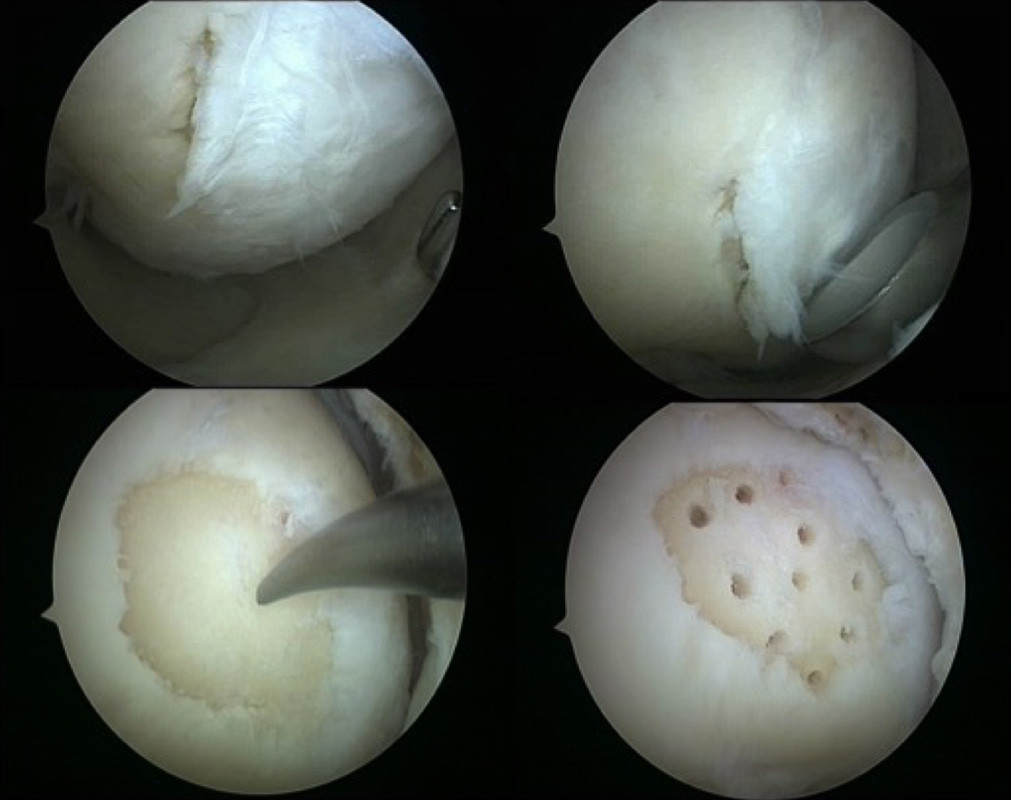

Mikrofrakturierung und Nanobohrung

Kleine, scharfbegrenzte, tiefergehende Defekt des Knorpels können durch einen sogenannten Mikrofrakturierung oder auch Nanobohrungen gedeckt werden. Hierbei werden zunächst alle losen Knorpelbestandteile entfernt und ein klar begrenzter Defekt geschaffen. Anschließend wird der freiliegende Knochen mit kleinen Meißeln oder Bohrern punktuell eröffnet.

Das aus dem Knochenmark austretende Blut ist reich an Stammzellen (Zellen die die Fähigkeit besitzen sich je nach Bedarf in unterschiedliche, spezialisierte Gewebezellen zu verwandeln) und füllt den Defekt zunächst mit einem Blutklumpen (Koagel) auf. Durch den Kontakt mit der Gelenkflüssigkeit und die im Gelenk herrschenden Scher- und Druckbelastungen wandelt sich dieses Blutkoagel in Ersatzknorpel (Faserknorpel) um und füllt den Defekt so auf. Dieser Eingriff erfolgt minimalinvasiv im Rahmen einer Gelenkspiegelung. Zum Schutz des sich neu bildenden Knorpels ist eine Entlastung für 6 Wochen mit einer anschließenden langsamen Belastungssteigerung erforderlich.

Technik der Mikrofrakturierung